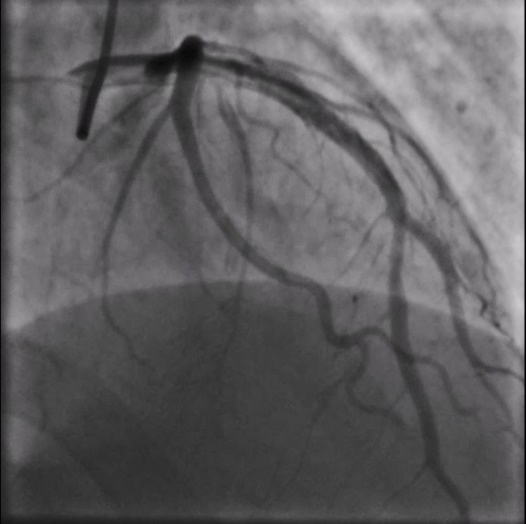

重庆江北区的65岁李先生反复心前区疼痛2年,半年前在外院前降支近端植入支架一枚,术后症状仍然反复,曾在多家医院就诊,无法明确原因。近日到新桥医院就诊,医院心血管内科为李先生安排了冠脉造影检查,结果提示:前降支支架内未见明显狭窄,但血流速度较正常冠脉明显变慢。

引起血流慢的原因何在?

二维平面的造影结果不能提供更多的信息,于是,新桥医院导管室主任赵晓辉教授决定采用高清IVUS技术(HD-IVUS,high definitionIntravascular ultrasound)对冠脉内结构进一步分析。结果显示支架梁近端开口处有一低密度斑块是引起慢血流的罪魁祸首。